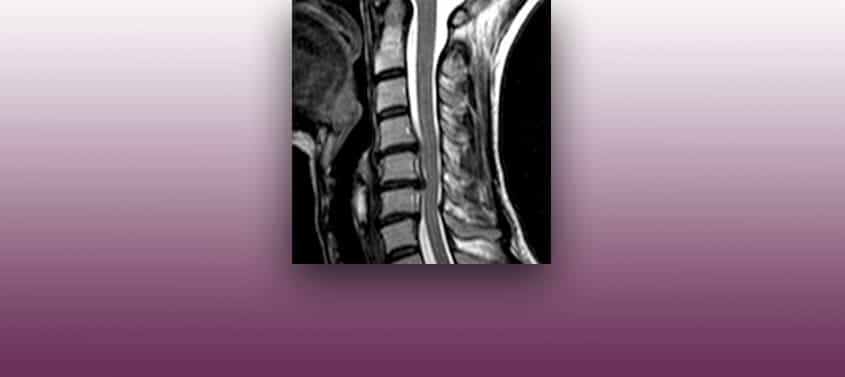

Przepuklina dysku szyjnego

Ostatnia aktualizacja: 20.02.2019, Dr. Miguel B. Royo Salvador, Katalog nr. 10389. Neurochirurg i Neurolog. DIAGNOZA Przepuklina lub wypuklina krążka międzykręgowego szyjnego może oddziaływać na korzenie nerwowe lub rdzeń kręgowy. Na tym poziomie kręgosłupa, dysk ma trochę więcej miejsca niż w odcinku piersiowym. Ze względu na większą częstotliwość występowania przepuklin szyjnych lub ucisku szyjno-artretycznego, dużo […]